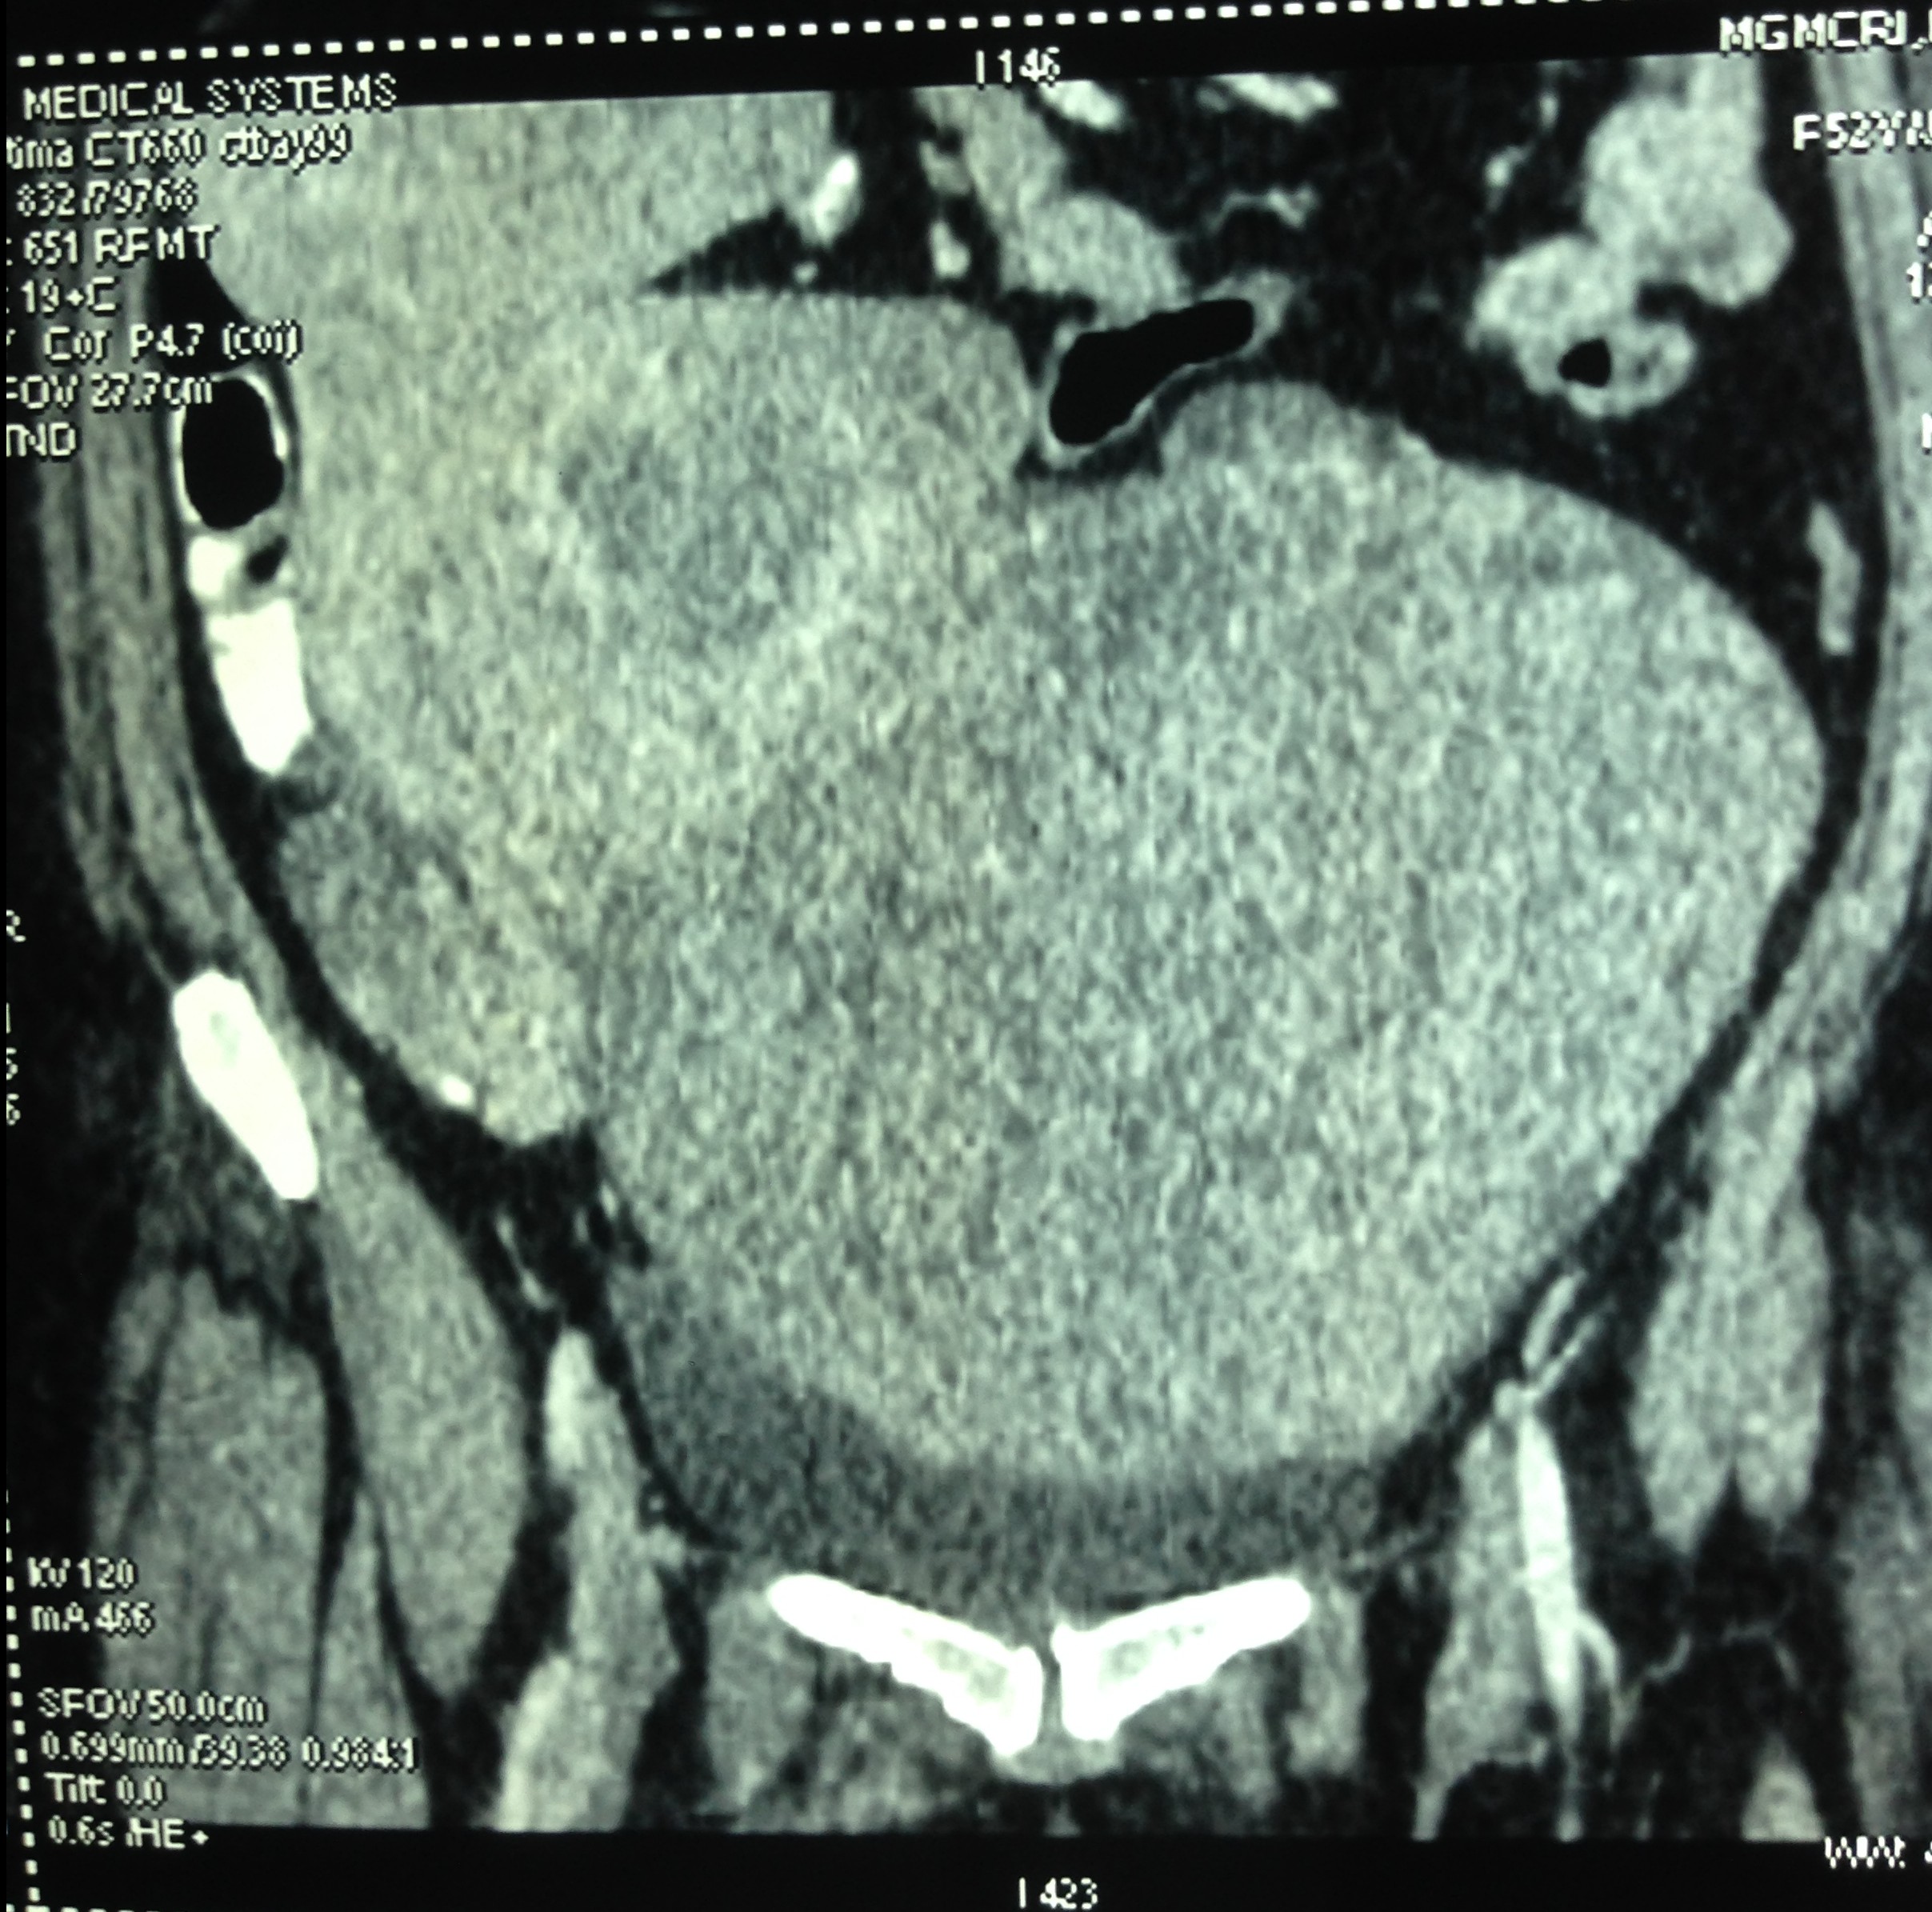

So a CT scan was done next . These pictures are reproduced here using a cell phone’s camera.

The following picture shows the enlarged uterus and large sub serous myomas extending upto the liver.

The large sub serous fibroids are seen below.